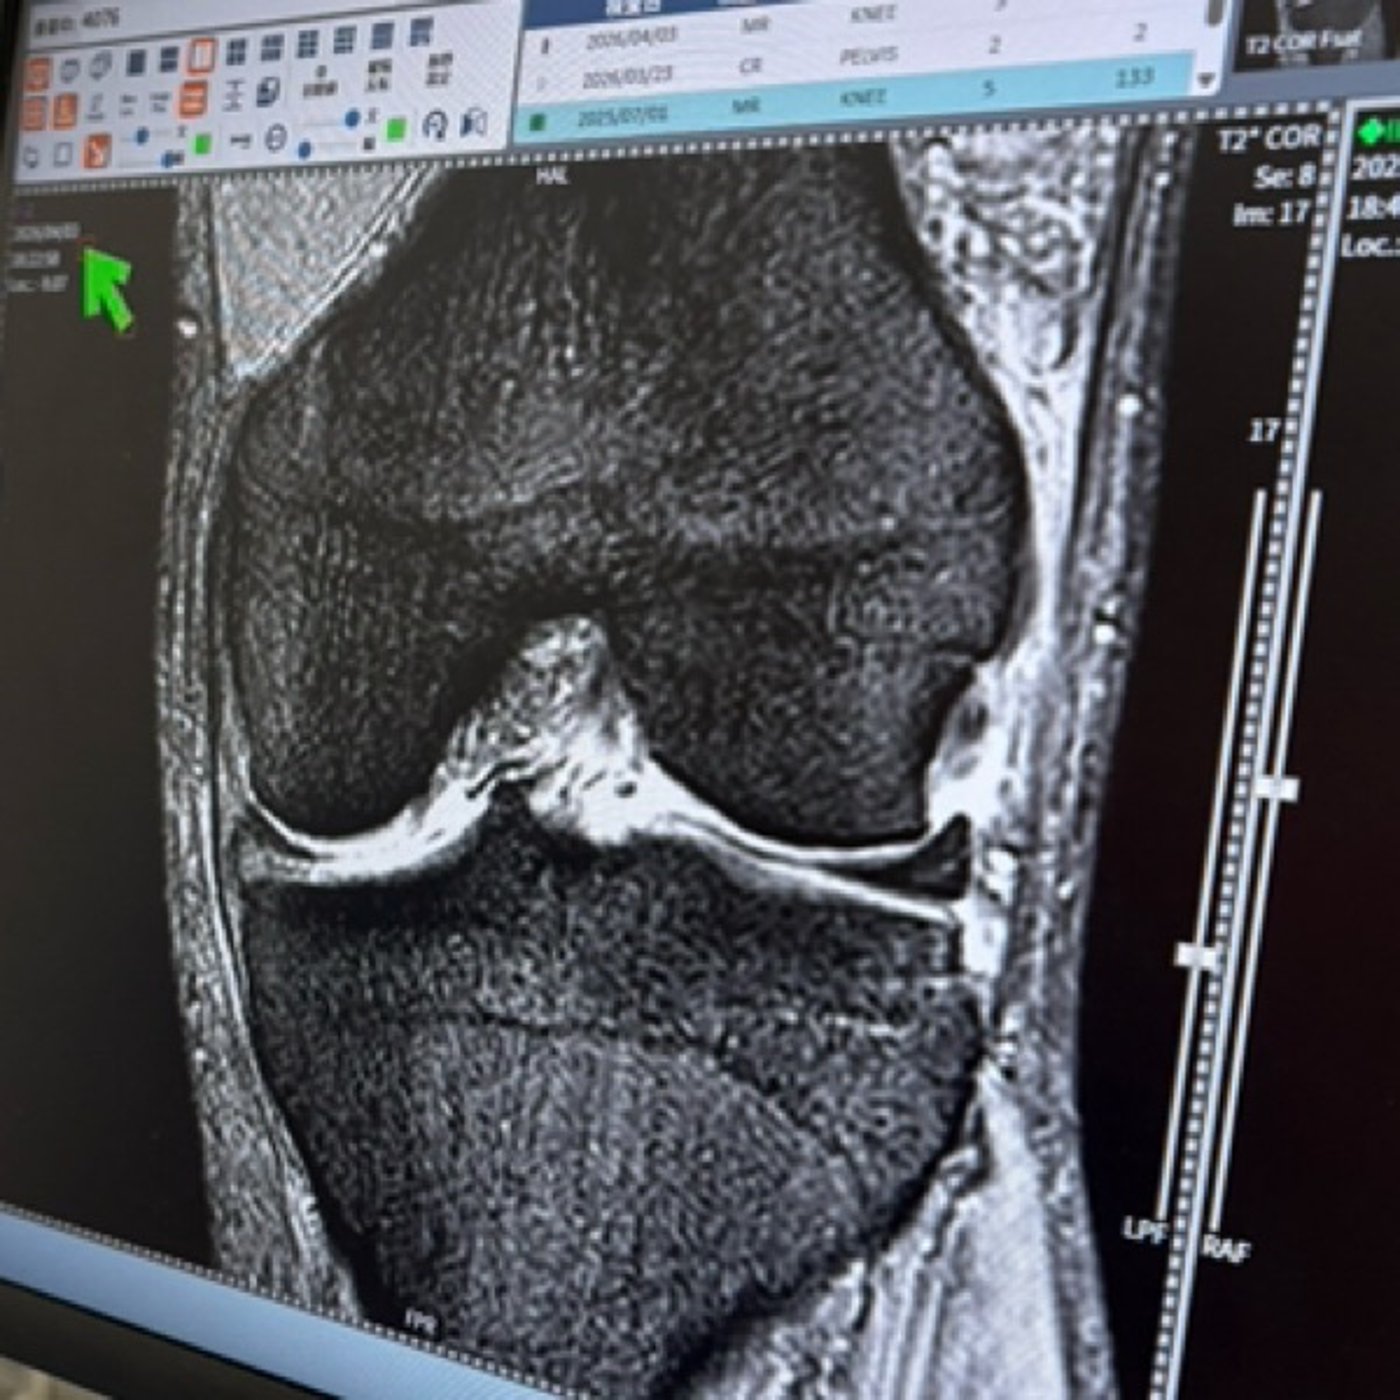

今日のラジオ📻は昨夜のMRI 検査結果と右足の歪みについてです!

なかなか珍しい症例と言われました🙄